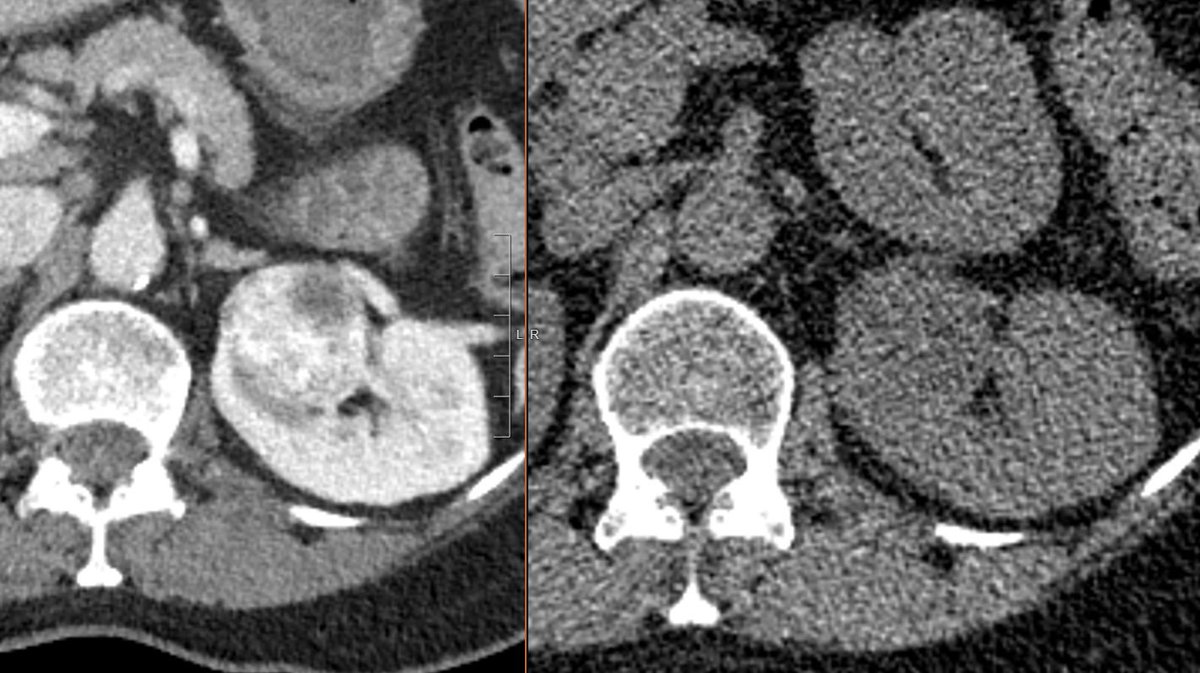

@WillyRontgen

RCC picked up by eagle eye on a low dose lung screen.